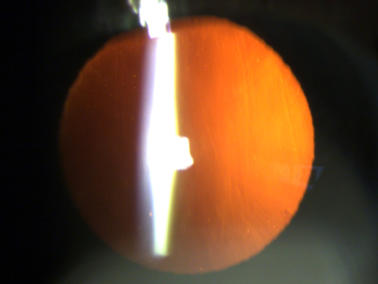

Klare Linse ohne Linsentrübungen

Eine Katarakt (links) verursacht ein unscharfes Bild durch vermehrte Lichtstreuung. Ein Linsen - tausch (rechts) korrigiert den Abbildungsfehler.

Eine Katarakt (links) verursacht ein unscharfes Bild durch vermehrte Lichtstreuung. Ein Linsentausch (rechts)  korrigiert den Abbildungsfehler.